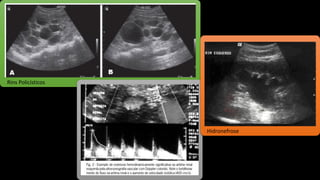

Alteração de Imagem

Radiografia simples de abdome

USG dos rins e vias urinárias

Tomografia

• rins policísticos;

• hidronefrose;

• cicatrizes corticais ou

alterações da textura cortical;

• sinais de doença infiltrativa;

• estenose da artéria renal

Rins Policísticos

Hidronefrose